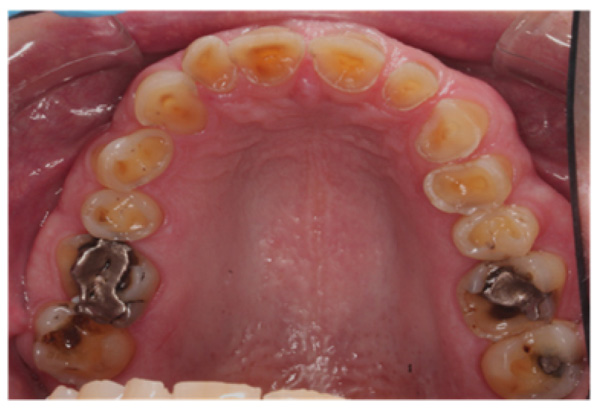

The patient presented with competent lips, an average lip line, normal TMJ function, and a mild Class II Division I incisor relationship with an increased overbite. The preoperative pan-oral radiograph is shown in Fig. (1). Boney exostoses and a large mandibular torus in the lower right mandible were present. The intra-oral presentation of the teeth is shown in Figs. (2-6). The patient had good oral hygiene and a healthy periodontium. The teeth had a glossy, smooth, and glazed appearance, showing cupping of the occlusal surfaces with significant loss of hard tissue and yellow color from the underlying dentine. This presentation was indicative of severe generalized tooth wear with exposed dentine in all sextants. The palatal, occlusal, and incisal surfaces were mainly affected, with lower buccal surfaces exhibiting more wear than the lower lingual, resulting in a reverse curve of Monson. The maximum BEWE score of 18 was recorded, meaning that the tooth with the most severe wear in each sextant had greater than 50% surface loss [9]. Several posterior teeth had amalgam restorations with defective margins (FDI 16, 26, 27, 37, and 47), as shown in Figs. (5 and 6). All teeth responded normally to pulp sensibility tests (cold test). The radiographs did not show any apical pathology to be present, but the pan-oral shows the scooped-out appearance of the lower molars.

IPS Empress Direct ® (Ivoclar Vivadent, Schaan, Liechtenstein) composite was syringed onto the worn surface and into the stent,which was seated onto the tooth. The composite was cured through the stent for 20 seconds; then the stent was removed, and the composite curing light was used again to ensure afull set for a further 40 seconds. The PTFE tape was removed, the excess composite at the gingival margin was trimmed back with narrow and ultra-fine diamond finishing burs, and a final polish was performed using Shofu Super-Snap Rainbow® discs (Kyoto 605-0983, Japan). The resultsare shown in Figs. (8-10). The slight increase in the vertical dimension is seen when comparing the pre-operative frontal image (Fig. 2) with the post-op image (Fig. 8), where some of the labial surfaces of the lower incisors is now visible, which was planned from the outset.